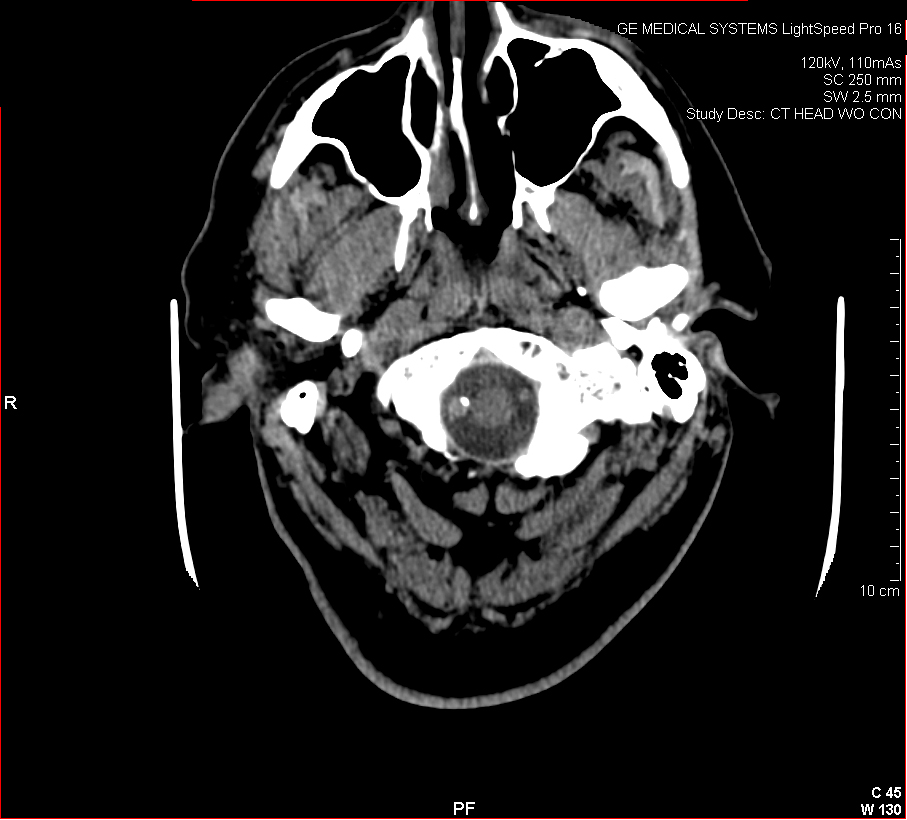

The images below show a CT scan of a traumatic head and neck injury, with a dissection of the right vertebral artery (left image) and a large stroke and intracerebral hemorrhage (ICH) with midline shift on the right side of the brain and a contusion overlying the skull (right image). (Images courtesy of Dr. McMurtrey)